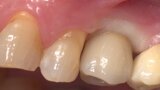

Conventional and immediate loading with final n!ce screw-retained crowns